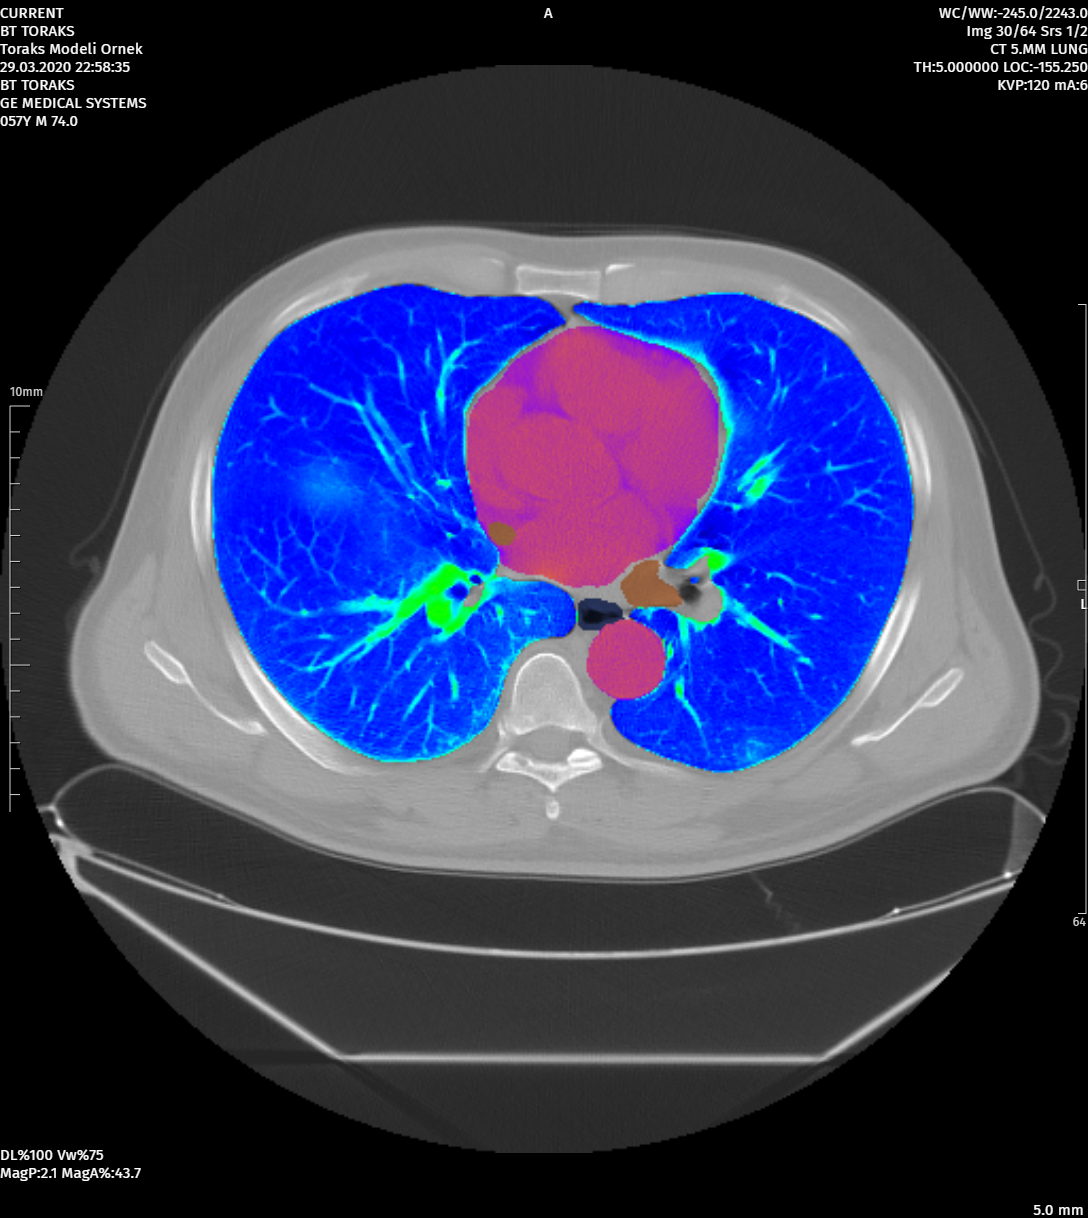

MoreAdvanced Image Processing Tools

Image Processing Tools That Can Work with Different Segmentations